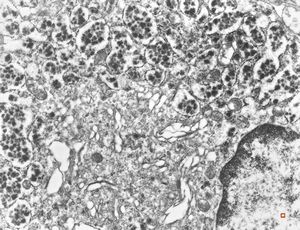

normal seromucinous salivary gland

oral saprophytic bacterium